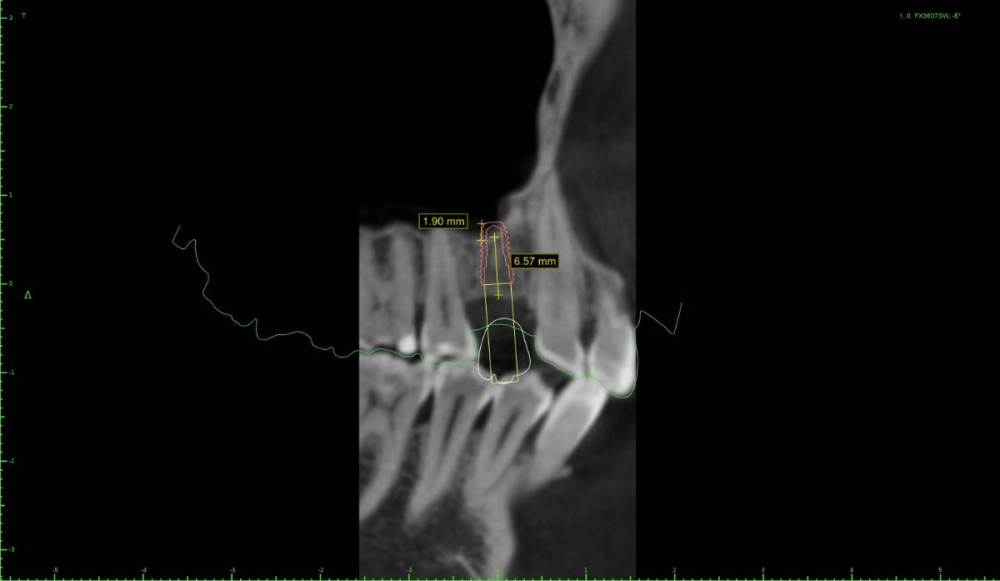

Женька Опубликовано 22 мая, 2021 Поделиться Опубликовано 22 мая, 2021 Дабы не захламлять тему про "мильён вопросов" я всё же создал свою. Итак, я получил оттиск верхней челюсти, отлил модель и перевёл в stl. Мои остеотомы застряли где-то в Пуяне и постучать нечем. Но в теме с мильёном вопросов пришли к выводу, что и зсл не нужен, только нкр. Что под рукой: даск с его фрезами для зсл, мембрана еволюшн, микс апатоса и только нитки, чтобы всё это зафиксировать. Также есть вариация имплантата суперлайн 2 (1.5мм полированной шейки и 5.5 шероховатой) или же полностью шероховатый суперлайн 1 с полированной фаской (3.6*7мм), но макродизайн менее агрессивный. Также будет сделан шаблон под пилотное сверление. Вот такие варианты получились. Вопрос, можно ли будет сделать маленькую нкр с имплантатом имеющим 1.5мм полированную шейку (как я понимаю - нет)? Ссылка на комментарий

Bier Опубликовано 3 июня, 2021 Поделиться Опубликовано 3 июня, 2021 я бы тут пластику не делал, только мягкие ткани. Ну имплантат в пазуху бы ткнул немного 1 Ссылка на комментарий

Женька Опубликовано 3 июня, 2021 Автор Поделиться Опубликовано 3 июня, 2021 @Bier позицию бы выбрали иначе, чем на снимках? Ссылка на комментарий

Bier Опубликовано 3 июня, 2021 Поделиться Опубликовано 3 июня, 2021 да, разумеется. ставил бы по кости. Ссылка на комментарий

Женька Опубликовано 3 июня, 2021 Автор Поделиться Опубликовано 3 июня, 2021 @Bier Олег Юрьевич, не могли бы вы нарисовать, пожалуйста как и куда. Имплантат 3.5 минимальный диаметр возможный... и либо 7 либо 8 мм. Ссылка на комментарий